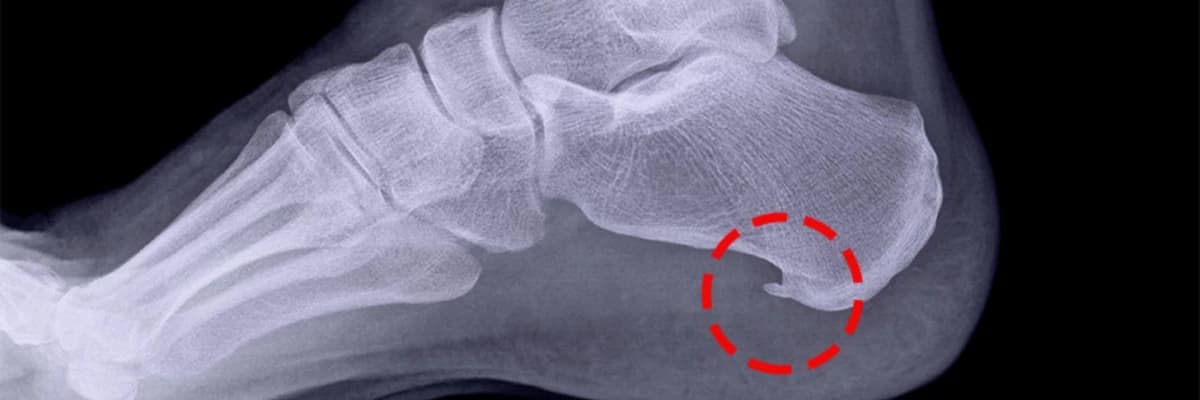

Daban çubuğu problemində ayaq altındakı əzələ kifayət qədər uzana bilmir və yükü yerə tam ötürə bilmədiyi üçün ağrı yaranır. Müxtəlif səbəblərdən bu əzələ qısalır və dabanın yerə dəydiyi hissəni dartmağa başlayır. Bu nöqtədə yaranan gərginlik bəzi hallarda qanaxmaya belə səbəb ola bilər. Zamanla həmin nahiyə qalınlaşaraq xaricə doğru çıxıntı yaradır və xalq arasında daban dikəsi kimi tanınan formanı alır.

Bu narahatlığın diaqnozu peşəkar ortopedik müayinə, rentgen və MRT (Maqnit Rezonans Tomoqrafiya) vasitəsilə qoyulur.